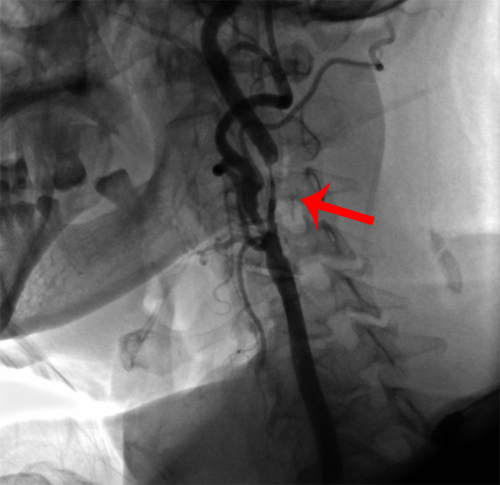

DSA示:双侧颈内动脉中度狭窄。

左侧颈内动脉中度狭窄